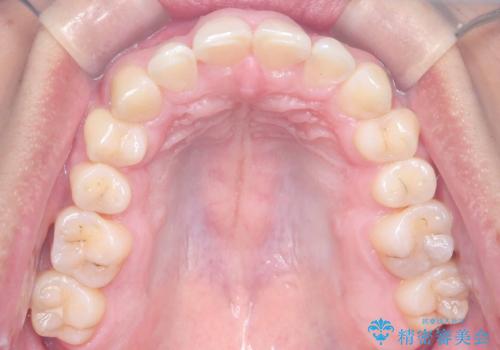

治療途中では咬み合わせの改善を目的としてバイトアップを行い、歯の捻転や叢生を改善しつつ、機能的に安定した咬合を獲得しています。

治療期間は3年2ヵ月と比較的長期となりましたが、見た目の歯並びだけでなく、咬み合わせまでしっかり整えた症例です。

上顎左右4番は90度捻転していたため、改善後歯根露出してしまっているためCTG(歯肉移植)を行う予定です。